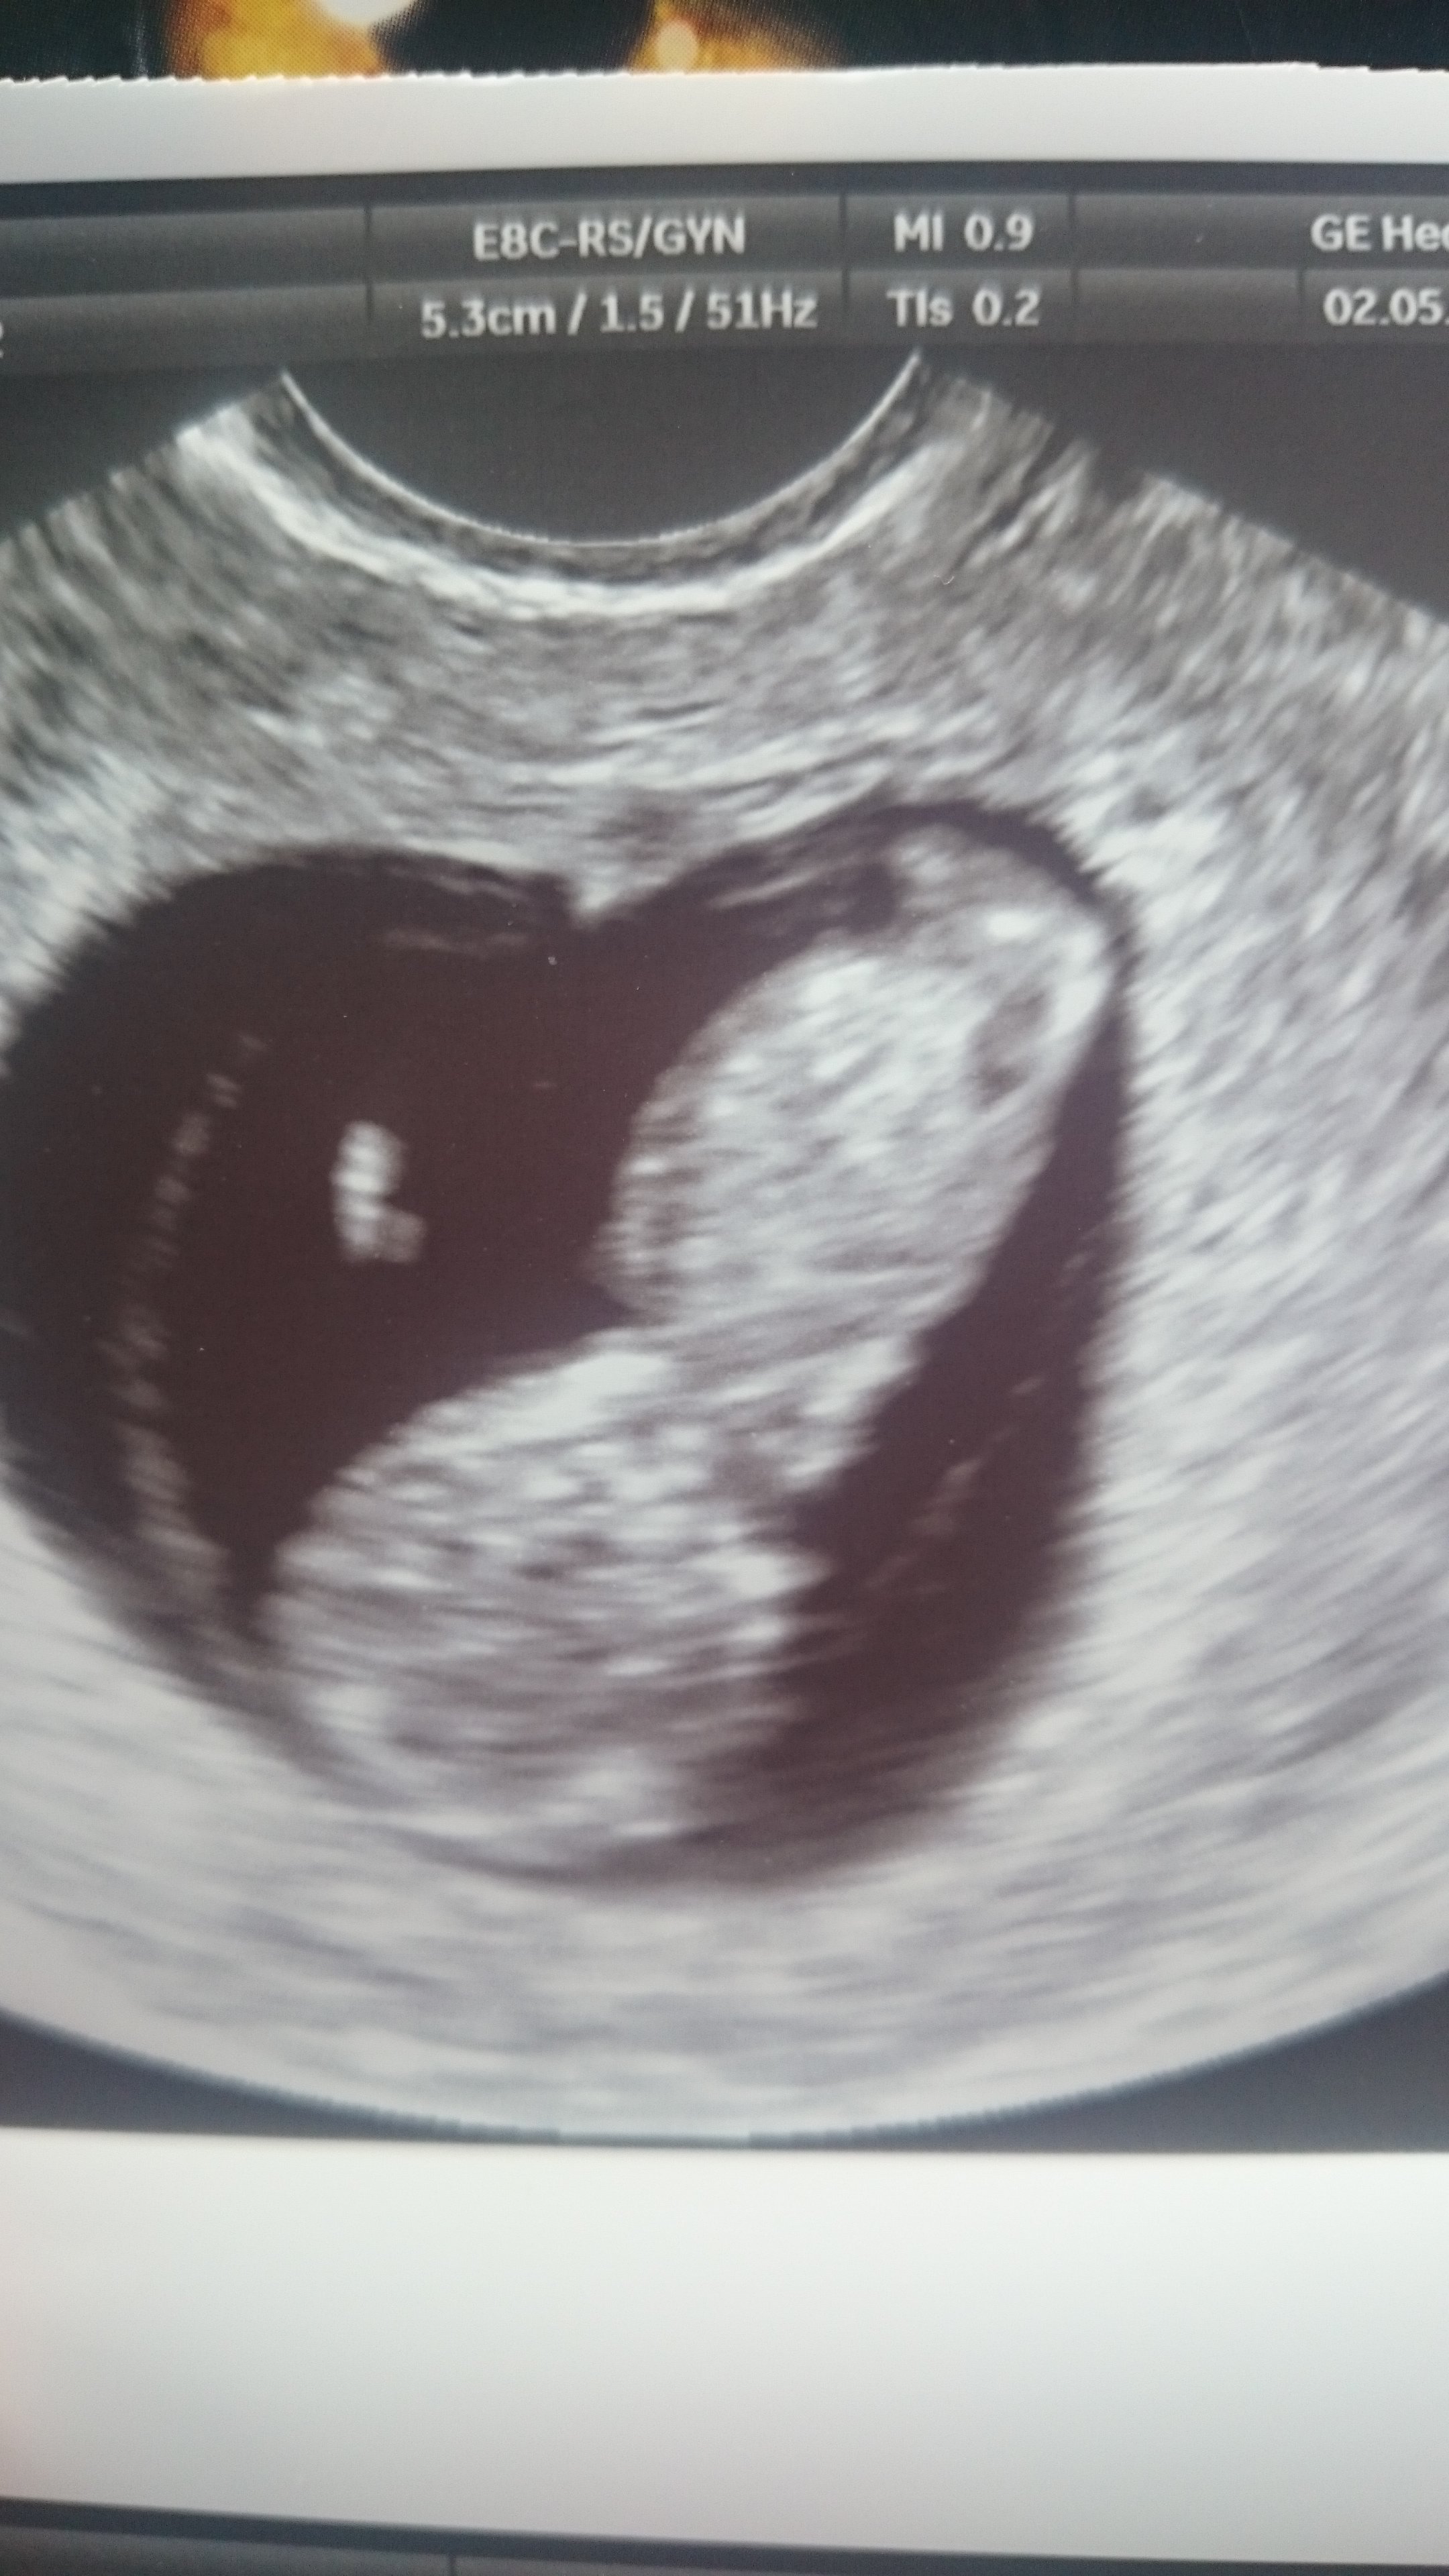

Super ☺Muszę się pochwalić.Jestem już po pierwszej wizycie u lekarza i z usg wyszło że mam 9tc❤❤❤ i termin na 5 grudnia widać i słychać jak serduszko bije

Super dzidzia gratulacje☺Zobacz załącznik 804782 Zobacz załącznik 804783 Zobacz załącznik 804784

My po wizycie

Na pierwszym zdjęciu widać rączkę, na drugim rączki, nóżki, na trzecim jest do góry nogami. Ruszał się, wręcz tańczył, serduszko tłucze jak szalone. Wszystko jest pięknie! Lekarz zachwycony, a my przeszczęśliwi![]()